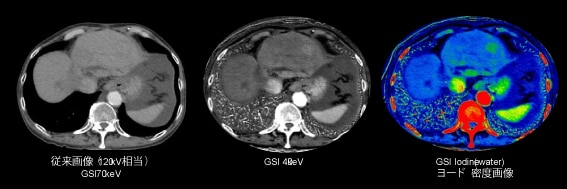

本製品では、従来のCT検査において主目的とされている形態評価にとどまらず、目的部位の機能情報の提供を実現しています。本製品では160mmカバレッジ、且つ最大1300mAが出力可能な次世代型Intelligent X線管球を搭載しており、電子ビームをmsec単位で集束・制御することで、管電圧ならびに管電流を変調させながら2つの異なるエネルギーデータを取得する(Synchronized kV/mA switching GSI)ことが可能です。

高エネルギーデータと低エネルギーデータをシグナルレベルで最適化させることで、低keV画像やヨード密度画像等MD画像の更なる高画質・高精度化を実現。低keV画像やヨード密度画像は、コントラストの向上が可能であるため、腫瘍の正確な描出、診断確信度の向上が期待でき、また従来CTでは得られなかった定量評価、付加価値の高い機能情報の提供を可能とします。

ビュー毎の管電圧のスイッチングに合わせて管電流も変調させるSynchronized kV/mA switching GSIの概念図

GSIでのヨードコントラスト強調画像による病変・関心部の描出能向上画像